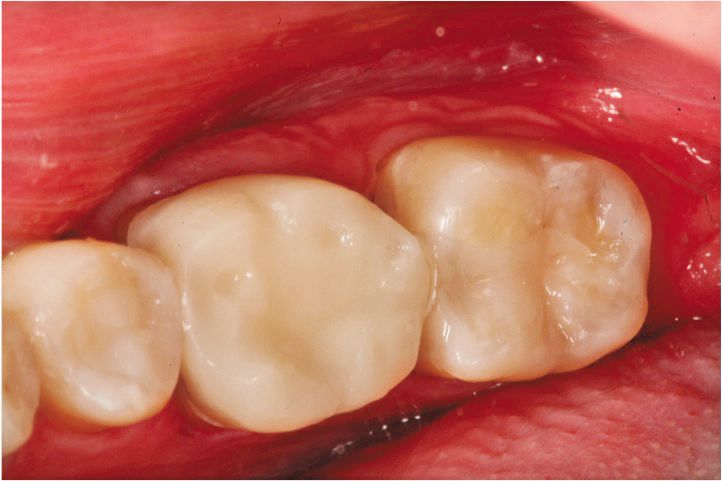

The patient presented with a lower right quadrant of mandibular teeth with existing defective restorations, interproximal caries, and in the case of the first molar, excessive occlusal wear. The treatment plan was: 1) A disto-occlusal direct composite restoration on tooth No. 29; 2) An indirect ceramic MOD onlay/crown for tooth No. 30; and 3) A mesio-occlusal direct composite restoration on tooth No. 31. The plan was to complete the composite restorations before master impression for tooth No. 30 to restore proper proximal contour to those teeth so the ceramist would have ideal proximal surfaces on tooth Nos. 29 and 31 to build to.